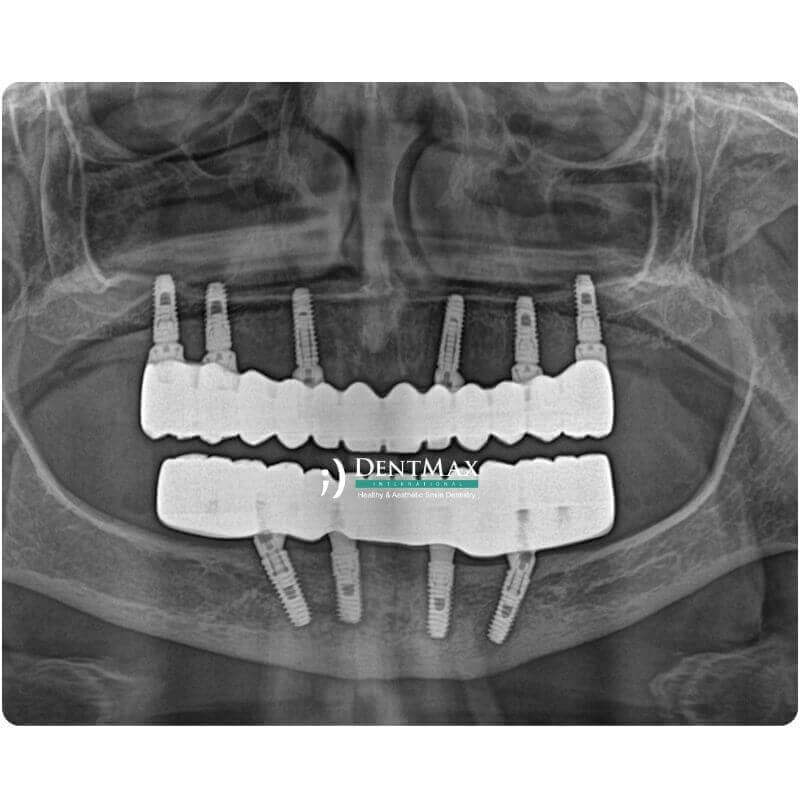

All-on-X implant tedavisi, tam dişsiz hastalar için çene başına 4, 5, 6, 7 veya 8 implant kullanılarak sabit diş protezlerinin uygulanmasını sağlayan ileri seviye bir implant çözümüdür. İstanbul’daki DentMax Diş Kliniği’nde, çene kemiğinin durumuna göre All-on-4, All-on-5, All-on-6, All-on-7 ve All-on-8 sistemleri kişiye özel olarak planlanır. Daha az implantla sabit diş isteyen hastalar için All-on-4 ekonomik ve hızlı bir çözüm sunarken, daha fazla implant kullanılan All-on-6, All-on-7 ve All-on-8 sistemleri uzun dönem konfor, dayanıklılık ve çiğneme gücü açısından daha yüksek stabilite sağlar.

All-on-X tedavisi, çene başına 4 ila 8 adet implant yerleştirilerek sabit tam çene protez uygulanmasını sağlayan bir tekniktir. All-on-4 sisteminde sadece dört implant ile ekonomik bir sabit çözüm sunulurken, All-on-5 ile orta düzey destek artırılır. All-on-6, klasik sabit protezlerin en yaygın uygulandığı sistemdir. All-on-7 ve All-on-8 ise daha fazla implant desteğiyle çiğneme kuvvetlerini daha dengeli dağıtarak uzun dönem stabilite sağlar.

Süreç, 3D tomografi ve dijital planlama ile başlar. Hastanın kemik durumu analiz edilerek en uygun sistem (All-on-4, All-on-6 vb.) belirlenir. Lokal anestezi altında implantlar yerleştirilir ve çoğu durumda aynı gün geçici sabit diş uygulanır. İyileşme süreci sonrası kalıcı zirkonyum ya da hibrit protezler hazırlanır.